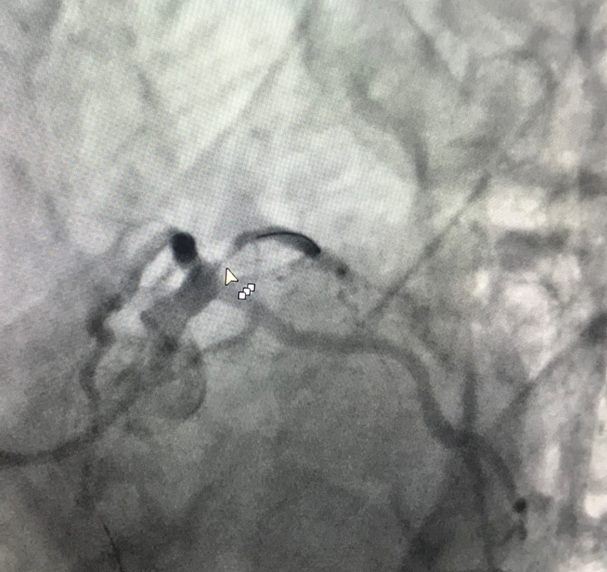

完善检查后,杨海涛副主任医师给予患者冠心病二级预防药物。效果一般,患者仍有症状。进一步为李先生冠脉造影显示:第一对角支80-90%狭窄。

杨海涛副主任医师联合冠心病四病区杨宏辉主任会诊后,立即为患者置入药物球囊,治疗后患者症状消失。